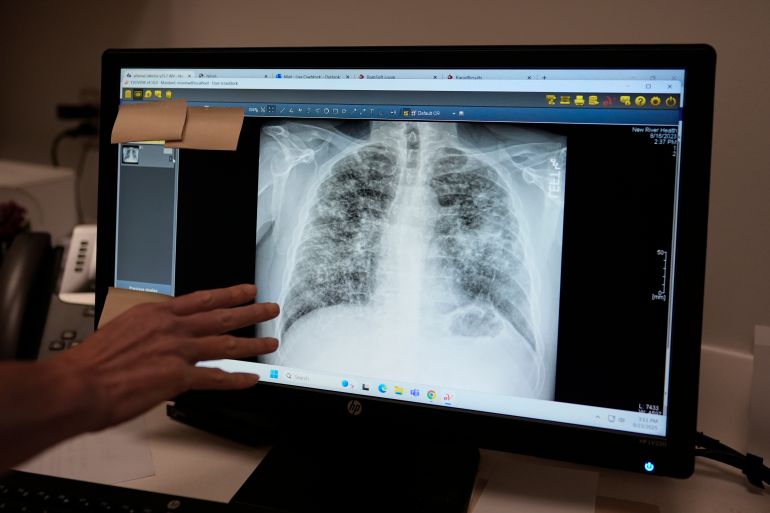

- فحص الرئة للمدخنين الشرهين:توصي فرقة الخدمات الوقائية الأمريكية بإجراء تصوير مقطعي منخفض الجرعة للرئة سنويا للبالغين من 50 إلى 80 عاما الذين لديهم تاريخ تدخين طويل -بمعدل علبة يوميا لمدة 20 عاما أو علبتين يوميا لمدة 10 سنوات- ويستمرون في التدخين أو أقلعوا خلال الـ15 عاما الماضية.